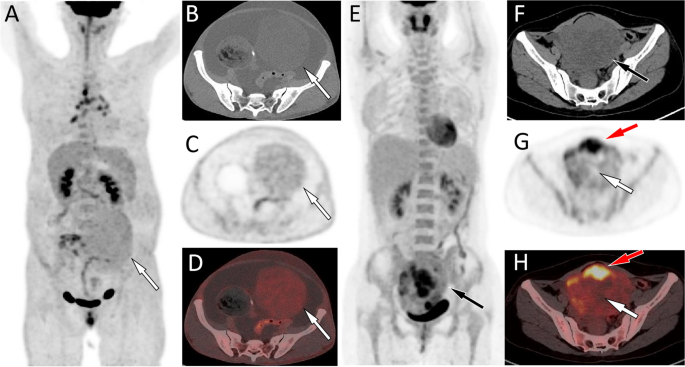

(A–D) Representative 18F-FDG PET/CT images of fibroma in a 59-year-old woman who admitted to hospital due to abdominal pain for 2 months. The maximum intensity projection (MIP, A) showed a slightly increased 18F-FDG uptake shadow in the lower abdomen (arrow). Axial CT of the corresponding site revealed a soft tissue mass of uniform density on the left side of the pelvic cavity (B, arrow). Axial PET (C) and PET/CT fusion (C) images showed a uniform and slightly increased 18F-FDG uptake, with a SUVmax of 2.2. (E–H) Another representative 18F-FDG PET/CT images of granulosa cell tumor (adults type) in a 45-year-old woman who admitted to hospital due to chest and abdominal pain for 2 weeks. The MIP (E) showed an increased 18F-FDG uptake shadow in the lower abdomen (arrow). Axial CT showed that the shadow was located in the pelvic cavity and was a soft tissue density mass (F, arrow). Axial PET (G) and PET/CT fusion (H, arrow) images showed varying degrees of increased uptake of 18F-FDG in the solid components of the tumor, with a SUVmax of 6.8 (red arrow), while the cystic area did not uptake 18F-FDG (white arrow). From these two representative cases, it can be seen that the SUVmax of granulosa cell tumors is significantly higher than that of fibromas.